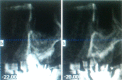

Materials and methods: Implant placement and maxillary sinus elevation were performed simultaneously. The location of the displaced implant was monitored for 8 years, until the ectopic implant was surgically removed using the lateral window approach. The contributing factors, treatment modality, and clinical outcome for our patient were compared with those of patients reported in the literature.

Conclusions: Transnasal endoscopic removal of an ectopic implant may be suitable in cases in which the ectopic implant is accessible. Transoral direct approaches are adequate in most cases in which endoscopic approaches may be confounded. The bony-window transoral technique may allow the removal of large implants.